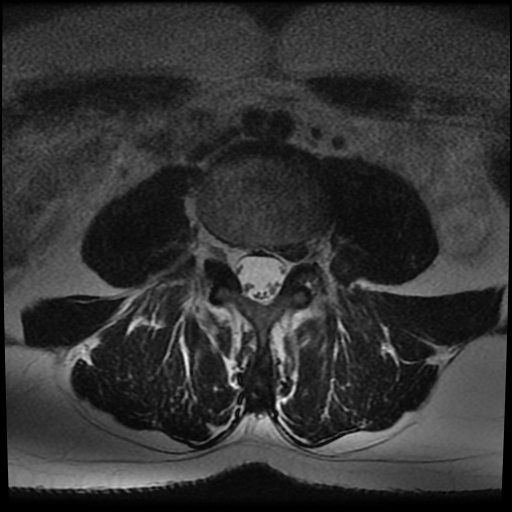

Vous avez fait réaliser une imagerie dont voici la coupe au niveau de l’articulation entre les vertèbres L5 et S1.